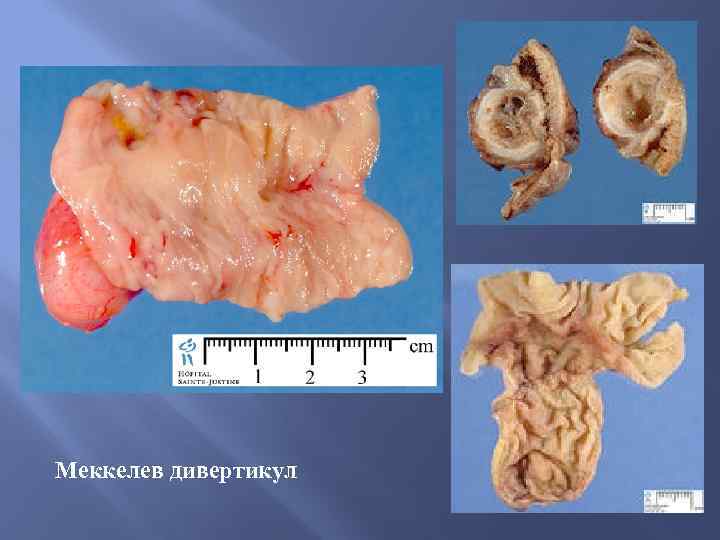

Меккелев дивертикул

Меккелев дивертикул

Меккелев дивертикул

Меккелев дивертикул

Меккелев дивертикул

Меккелев дивертикул